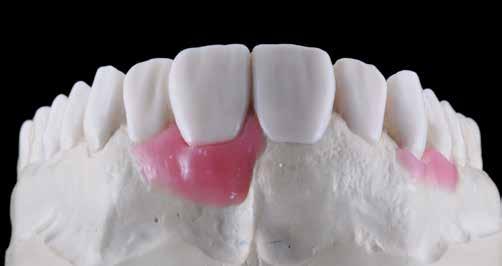

A kezelések második fázisában a pácienssel közösen non-prep/ minimálinvazív héjak készítése mellett döntöttünk (6. és 7. ábra).

Az ilyen jellegű ellátás során csupán a lehető legkisebb mennyiségű foganyag kerül eltávolításra. A minimálinvazív beavatkozás elvégzését lehetővé tevő feltételeket a fogszabályzó kezelés során alakítottuk ki. A fogazat minimálinvazív módon készített héjakkal történő ellátásához a fogaknak olyan pozícióban kell lenniük, amely lehetővé teszi az esztétikai megjelenés additív eljárások alkalmazása mellett történő optimalizálását. Azonban az ellátás során előbbiekben felsoroltakon kívül más szempontokat is figyelembe kell vennünk. Amennyiben a páciens a jelenleg látható fogszínéhez képest jelentős változást szeretne elérni, úgy sokkal vastagabb héjak készítésére van szükség, és az ezáltal megnövekedett helyigény miatt sok esetben nincs lehetőség kizárólag additív eljárások alkalmazására (8. ábra). Mivel a cikkben bemutatásra kerülő eset ellátása során a fogazat helyzeti rendellenességei az előzetes orthodonciai kezelés keretei között korrekcióra kerültek, ezért lehetőségünk adódott a restauratív fázis minimálinvazív módon történő elvégzésére. Az általunk alkalmazott terápia hátrányai között szerepelt, hogy az elvégzett beavatkozások időigénye miatt a tervezett végeredményt csupán viszonylag hosszú idő után tudtuk elérni.

A fogazat minimálinvazív módon készített héjakkal történő ellátásához a fogaknak olyan pozícióban kell lenniük, amely lehetővé teszi az esztétikai megjelenés additív eljárások alkalmazása mellett történő optimalizálását.1. ábra: Kiindulási állapot. A felső nagymetszőfogak élharapásban vannak. 2. ábra: Az orthodonciai kezelés megkezdése előtt készített intraorális felvétel. A páciens csak óvatosan mer mosolyogni. 3. és 4. ábra: Digitálisan megtervezett kezelés.